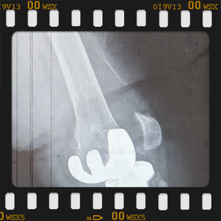

Eklem yüzeyleri özel kılavuzlar yardımı ile temizlendikten sonra metal protez eklem yüzeylerine bir kemik çimentosu ile adapte diyoruz. Bu iki metal yüzeyin sürtünmesini azaltmak için polietilenden yapılmış özel bir plastik tabakayı sisteme dahil ediyoruz.

Büyütmek için üzerine tıklayınız.